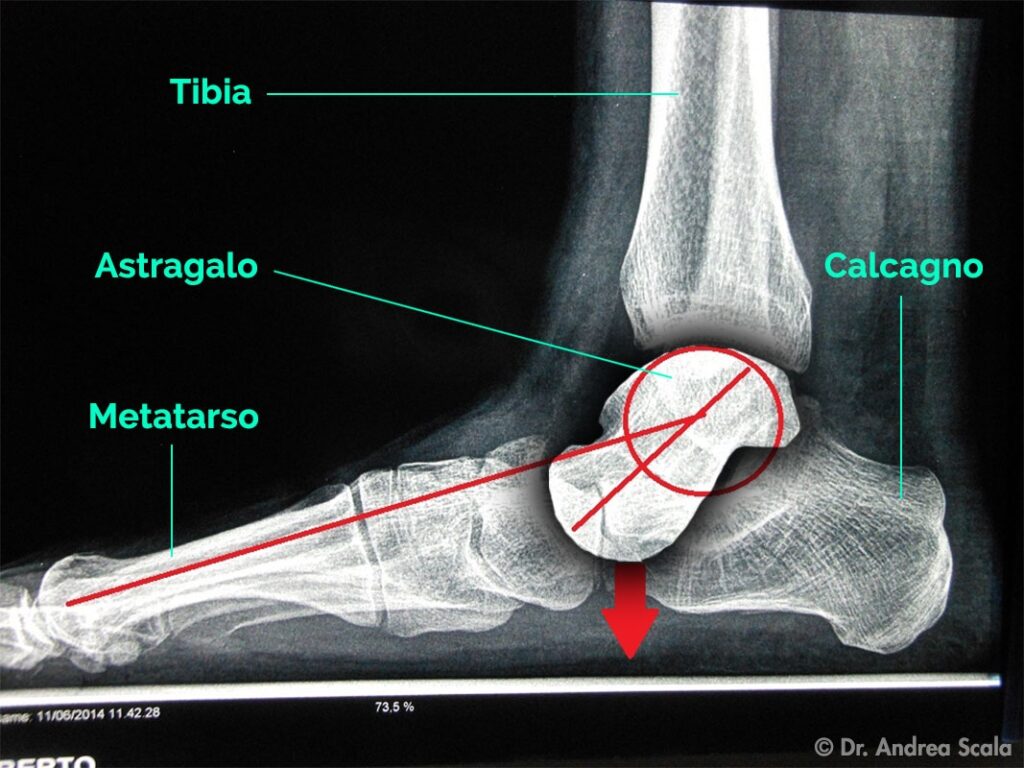

La radiografia pre-operatoria mostra il crollo dell’arco interno del piede. La freccia rossa indica che l’ astragalo crolla verso il suolo (piede valgo pronato). La linea rossa che viene dal metatarso è spezzata e dimostra che il piede è praticamente rotto in due parti: anteriore (avampiede) e posteriore (retropiede).